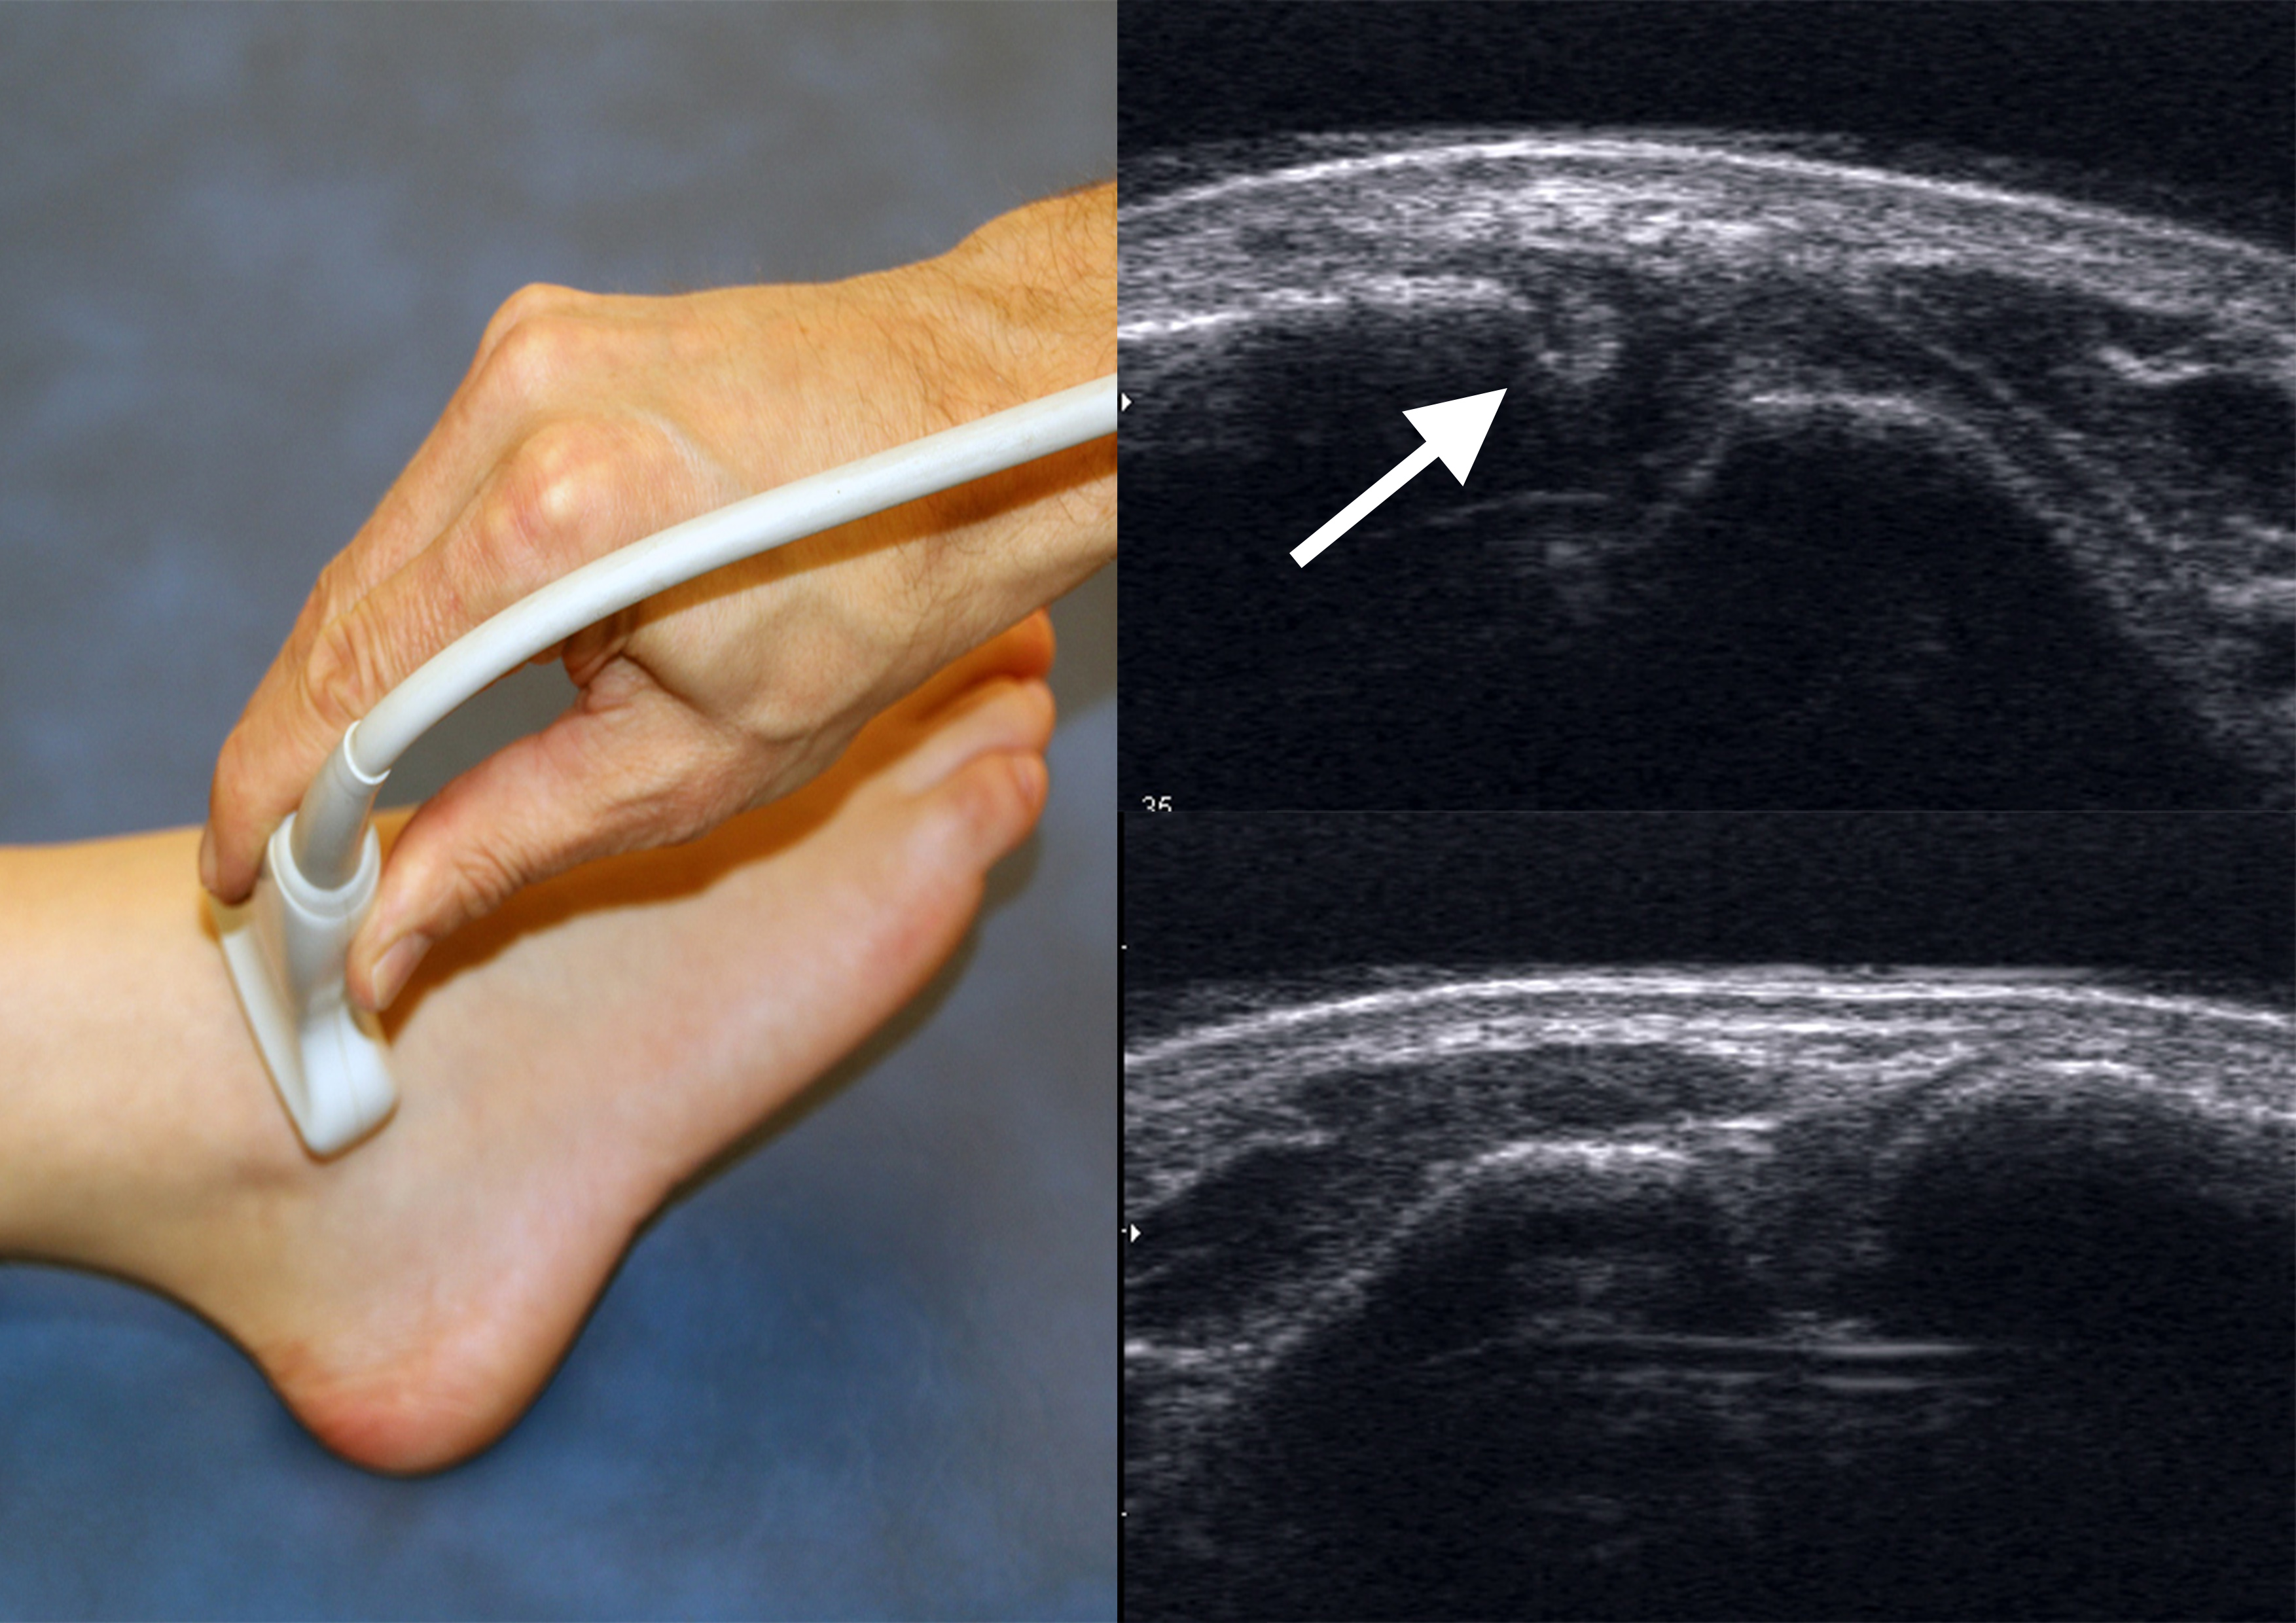

Ultraschall

Studien konnten zeigen, dass die dynamische Ultraschalluntersuchung eine sehr hohe Sensitivität und Spezifität zur Beurteilung von Syndesmosenverletzungen hat 37. Auf Höhe der Syndesmose wird dabei die coronare Translation der Fibula gegenüber der Tibia im Vergleich zur Gegenseite beurteilt. Obwohl die dynamische Ultraschalluntersuchung ein sehr präzises und kostengünstiges Diagnostikmittel ist, setzt sie ein hohes Maß an Übung voraus. Darüberhinaus können Begleitverletzungen wie zum Beispiel Osteochondrale Läsionen oder Knochenmarködeme nicht detektiert werden 38.

Quelle Abbildung 4: Sonographische Diagnostik an Sprunggelenk und Fuß , H. Gaulrapp